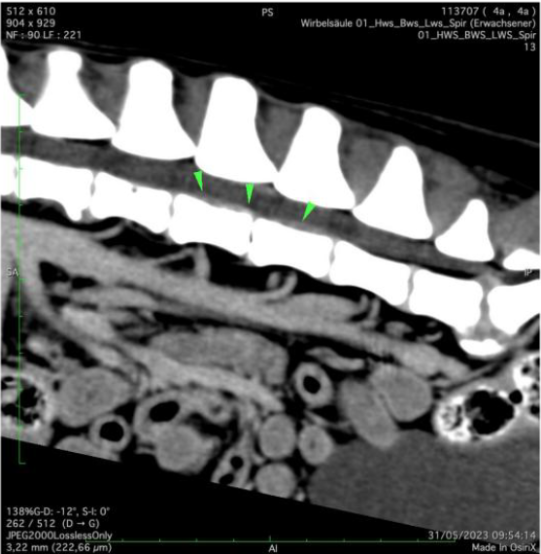

Der Patient wird neurologisch untersucht. Er ist hinten kraftlos und zeigt eine stark reduzierte Schmerzempfindlichkeit sowie einen Koordinationsverlust beider Hinterbeine. Die Kniescheibenreflexe sind gesteigert. Zusammengefasst weisen die Befunde auf eine Störung im Bereich des Lenden-Rückenmarkes hin; aufgrund des akuten Auftretens und der Rasse des Hundes steht die Verdachtsdiagnose eines Bandscheibenvorfalls im Vordergrund. Der Hund wird notfallmässig an ein Spital überwiesen, wo ein Computer-Tomogramm der Wirbelsäule angefertigt wird. Hier wird ersichtlich, dass das Tier tatsächlich an einem akuten Bandscheibenvorfall leidet: Teile der Bandscheibe zwischen dem 4. und 5. Lendenwirbel sind in den Rückenmarkskanal gequetscht worden und drücken auf die empfindlichen Nervenbahnen (grüne Pfeile). Der Rüde wird operiert, das Bandscheibenmaterial wird mittels einer sogenannten Hemilaminektomie entfernt.